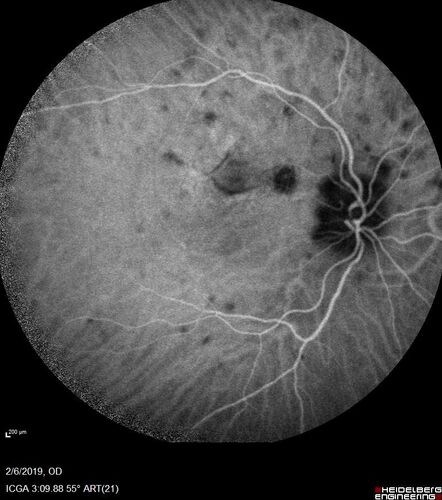

PIC which evolved into Subretinal Fibrosis

27 year old female VA 20/200 right eye 20/20 left eye. Right was treated with lucentis. When extended to 3 months, the fibrosis got much worse